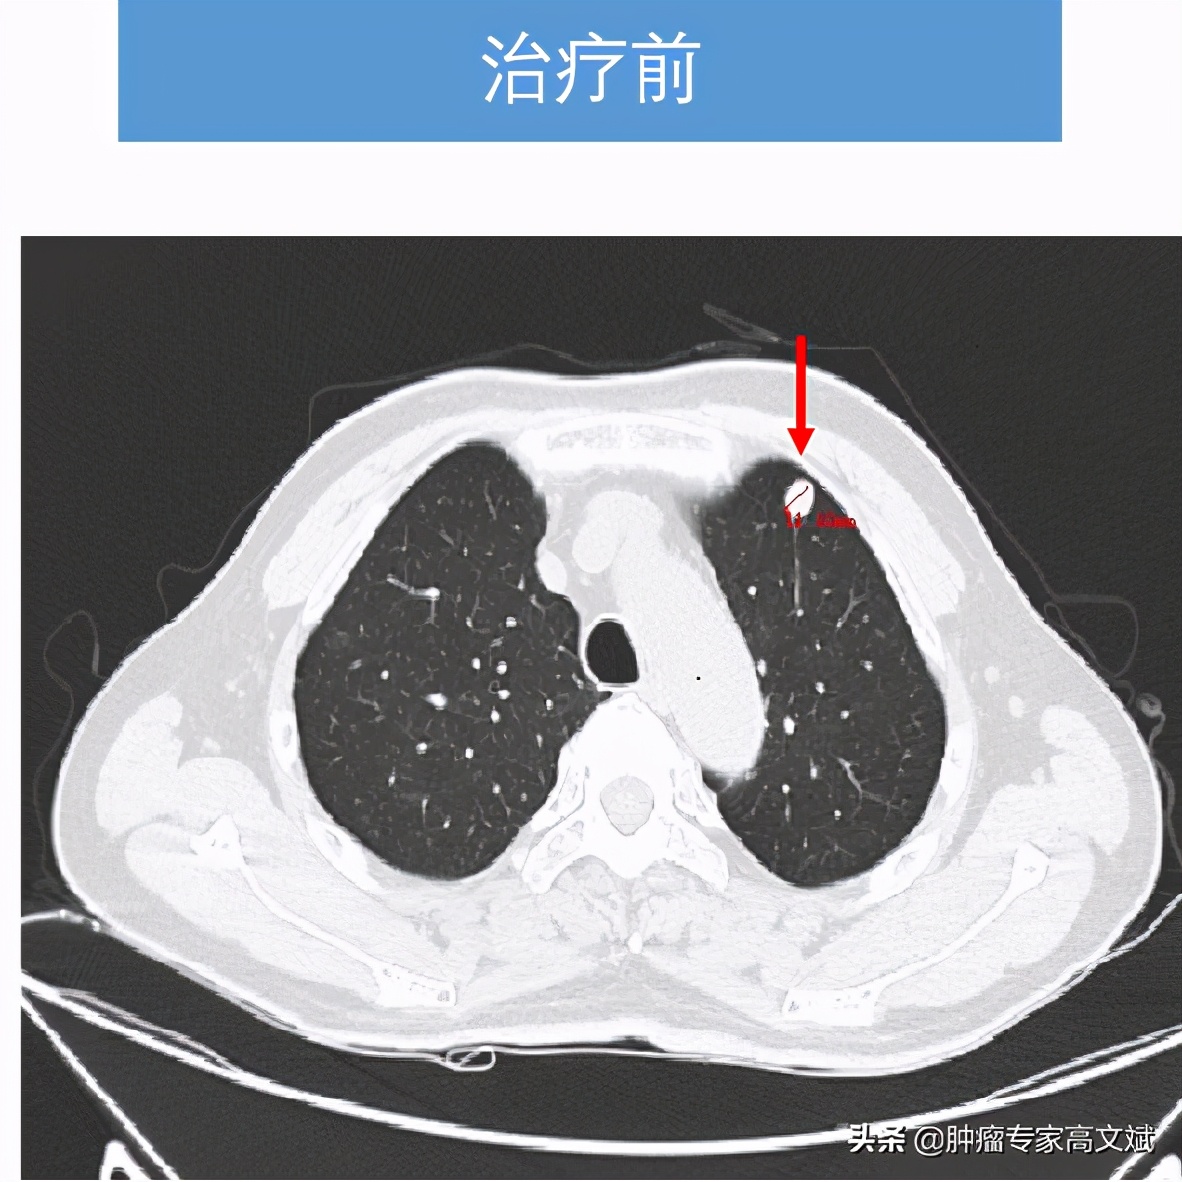

患者老陈今年58岁了,10个月以前在外院发现肝右叶占位,临床诊断为原发性肝癌,由于没有手术治疗的机会,患者在外院实施了一系列的非手术治疗,包括PVL、TACE治疗等,还口服了仑法替尼靶向治疗了2个多月。患者这边的治疗是一刻也没有停,肿瘤那边是生长也一直没有停,就这样患者来我们科的时候,肝右叶肿物较前已经是明显的增大、增多,肝右叶最大的肿瘤已经是16.2cm×10.7cm×9.5cm大小,静脉癌栓也增多,双肺出现了新发转移灶。由于持续性的治疗,患者对于治疗已经失去了信心,只是要求别让他太疼痛即可,茶不思饭不想的他已经不期待什么治疗的疗效了。

看着患者的一般情况还好,所谓的身体状况不佳主要还是前边治疗的不良反应所导致的。我们还是决定给患者实施一个单药的免疫治疗来控制肿瘤的生长,又不过分增加患者的不良反应。就这样患者也接受了我们的建议,我们为患者实施了国产的免疫制剂卡瑞利珠单抗(艾瑞卡)200mg,每2周一次使用。让我们没有想到的是,患者治疗2个周期以后,肿瘤标志物AFP出现了陡坡样的下降,肝脏疼痛也出现了缓解,每天躺在床上的老陈已经开始下床活动,饮食量等情况也明显的改善,对于治疗患者也有了明显的信心。就这样,治疗了8个周期以后,老陈的肝脏肿瘤明显缩小了,肺内转移灶也有消失,肿瘤标志物则是更早地恢复了正常,止痛药也完全的不再使用了。对于老陈来说,剩下的事情就是每月来罗湖医院肿瘤科输注两次卡瑞利珠单抗(艾瑞卡)就可以了。